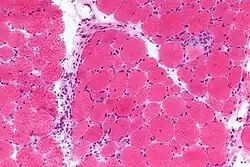

- Examining a muscle biopsy under a microscope and finding mononuclear white blood cells between the muscle cells, and finding abnormal muscle cell degeneration and regeneration, dying muscle cells, and muscle cells being consumed by other cells (phagocytosis)

The pathogenesis of dermatomyositis involves an autoimmune-mediated process characterized by immune complex deposition and complement activation, leading to microangiopathy in both muscle and skin tissues. The specific mechanism of tissue injury is variable, depending on the specific autoantibodies and immune cell types involved.[16] The microangiopathy has a non-uniform pattern: within a single muscle fiber, some capillaries may be heavily affected while others seem to be unharmed.[17]

In contrast to polymyositis, which pathologically centers on damage to the endomysium of muscle fibers, dermatomyositis damages both the endomysium and the perimysium. This indicates that tissue damage from dermatomyositis is not limited to the capillaries and the tissues immediately surrounding them; it also damages the larger vessels of the muscle fibers and skin tissue, potentially causing wider structural damage.[17]